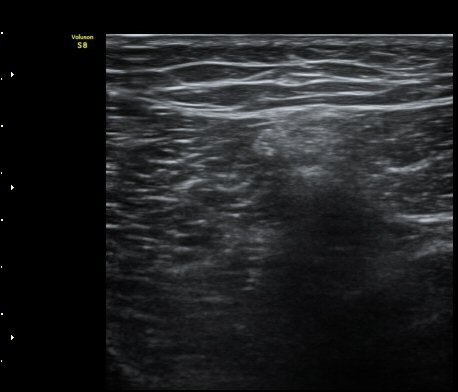

´ëÅð ³»Ãø, ¹«¸­ °üÀý¸é¿¡¼­ ¾à 10 cm ±ÙÀ§ºÎȾ´Ü¸é°Ë»ç¿¡¼­ ³»Ãø±¤±Ù°ú ºÀRHD±Ù(sartorius)

»çÀÌ¿¡¼­ º¹Àç½Å°æÀÌ °í¿¡ÄÚ Å¸¿øÇü ¾ç»óÀ¸·Î °í³ªÂûµÈ´Ù(»çÁø 2).